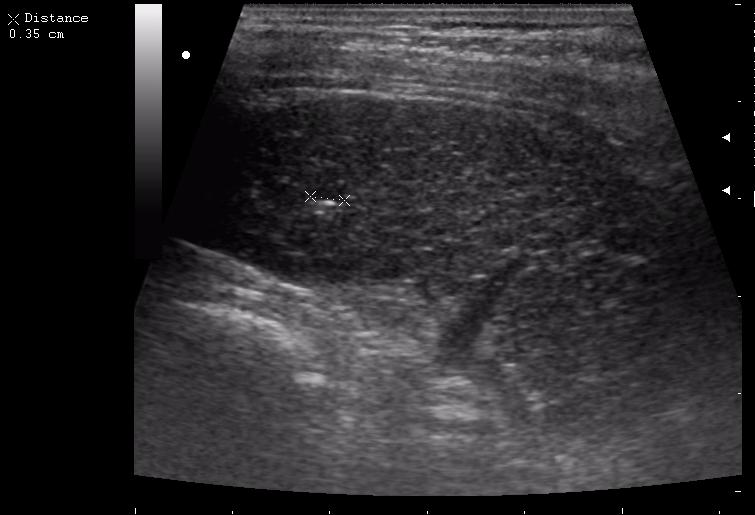

наезд большой черной Прады на маленькую (13кг) 5-летнюю девочку.

получает Медаксон, рабочая версия - изменение желчного пузыря вследствии травмы (шепотом - рекомендация хирургу сменить антибиотик)